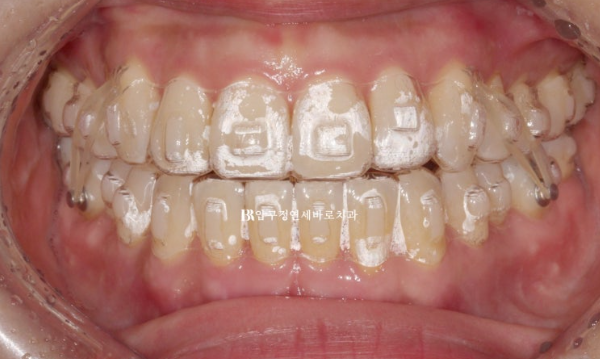

첫세트의 장치는 총 23개가 제작이 되었고 5개월에 걸쳐 장치를 다 낀 후 모습입니다.

23.10

중심선도 맞고 개방교합이 해소가 되었습니다.

다만 교합과 배열상 아쉬운 부분이 있어서 재제작에 들어갔습니다.